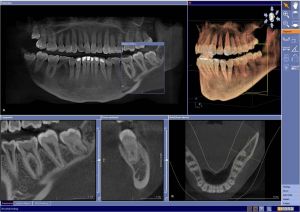

In der Implantologie hat die Diagnostik und Behandlungsplanung unter Experten ein neues Niveau erreicht, das dem Patienten entscheidende Vorteile bietet. Die dreidimensionale Aufnahmemöglichkeit mittels Digitaler VolumenTOMOGRAPHIE (DVT) ist ein Meilenstein der Sicherheit und Genauigkeit bei implantatchirurgischen und implantologischen Behandlungen.

Schnell und unkompliziert

Bei diesem strahlungsarmen Verfahren werden hunderte digitaler Röntgenaufnahmen innerhalb einer kurzen Zeitspanne geschossen, die vereint ein dreidimensionales Bild des Kiefers und der Zähne ergeben. Anders als bei herkömmlichen 2-D Schichtungsverfahren erhält der Implantatexperte beim DVT eine komplette Durchsicht der zu untersuchenden Gewebe. So ist es ihm möglich, die komplexesten Eingriffe präzise zu planen und durchzuführen. Und das bei extrem geringer Strahlenbelastung für den Patienten.

Die Vorteile für den Patienten sind enorm: Durch eine exakte Behandlungsplanung und äußerst präzise Diagnostik ermöglicht das DVT:

Das alles bei extrem reduzierter Strahlung gegenüber einem CT (Computer Tomogramm) und komfortabel ohne die klassische CT-Situation „in der Röhre”, sondern bequem und schnell wie beim gewöhnlichen zahnärztlichen Röntgen.